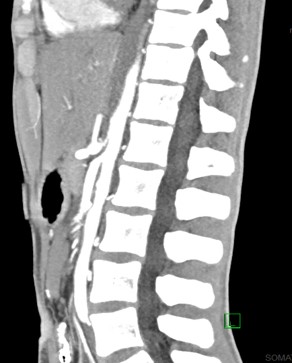

Computed tomography downloaded from Occupational Safety and Health

CT Scan

YouTube link for the initial CT scan is available at https://youtu.be/jG0J2b3EhhU.

Impression

Extensive air surrounded the esophagus and within the mediastinum, with dissecting along soft tissue planes, as described, suggestive of an esophageal perforation.

There is no free air in the abdomen. There is dilated stomach and proximal duodenum, with narrowing of the duodenum as it crosses the superior mesenteric artery (SMA). This can be seen with SMA syndrome in the proper clinical setting.